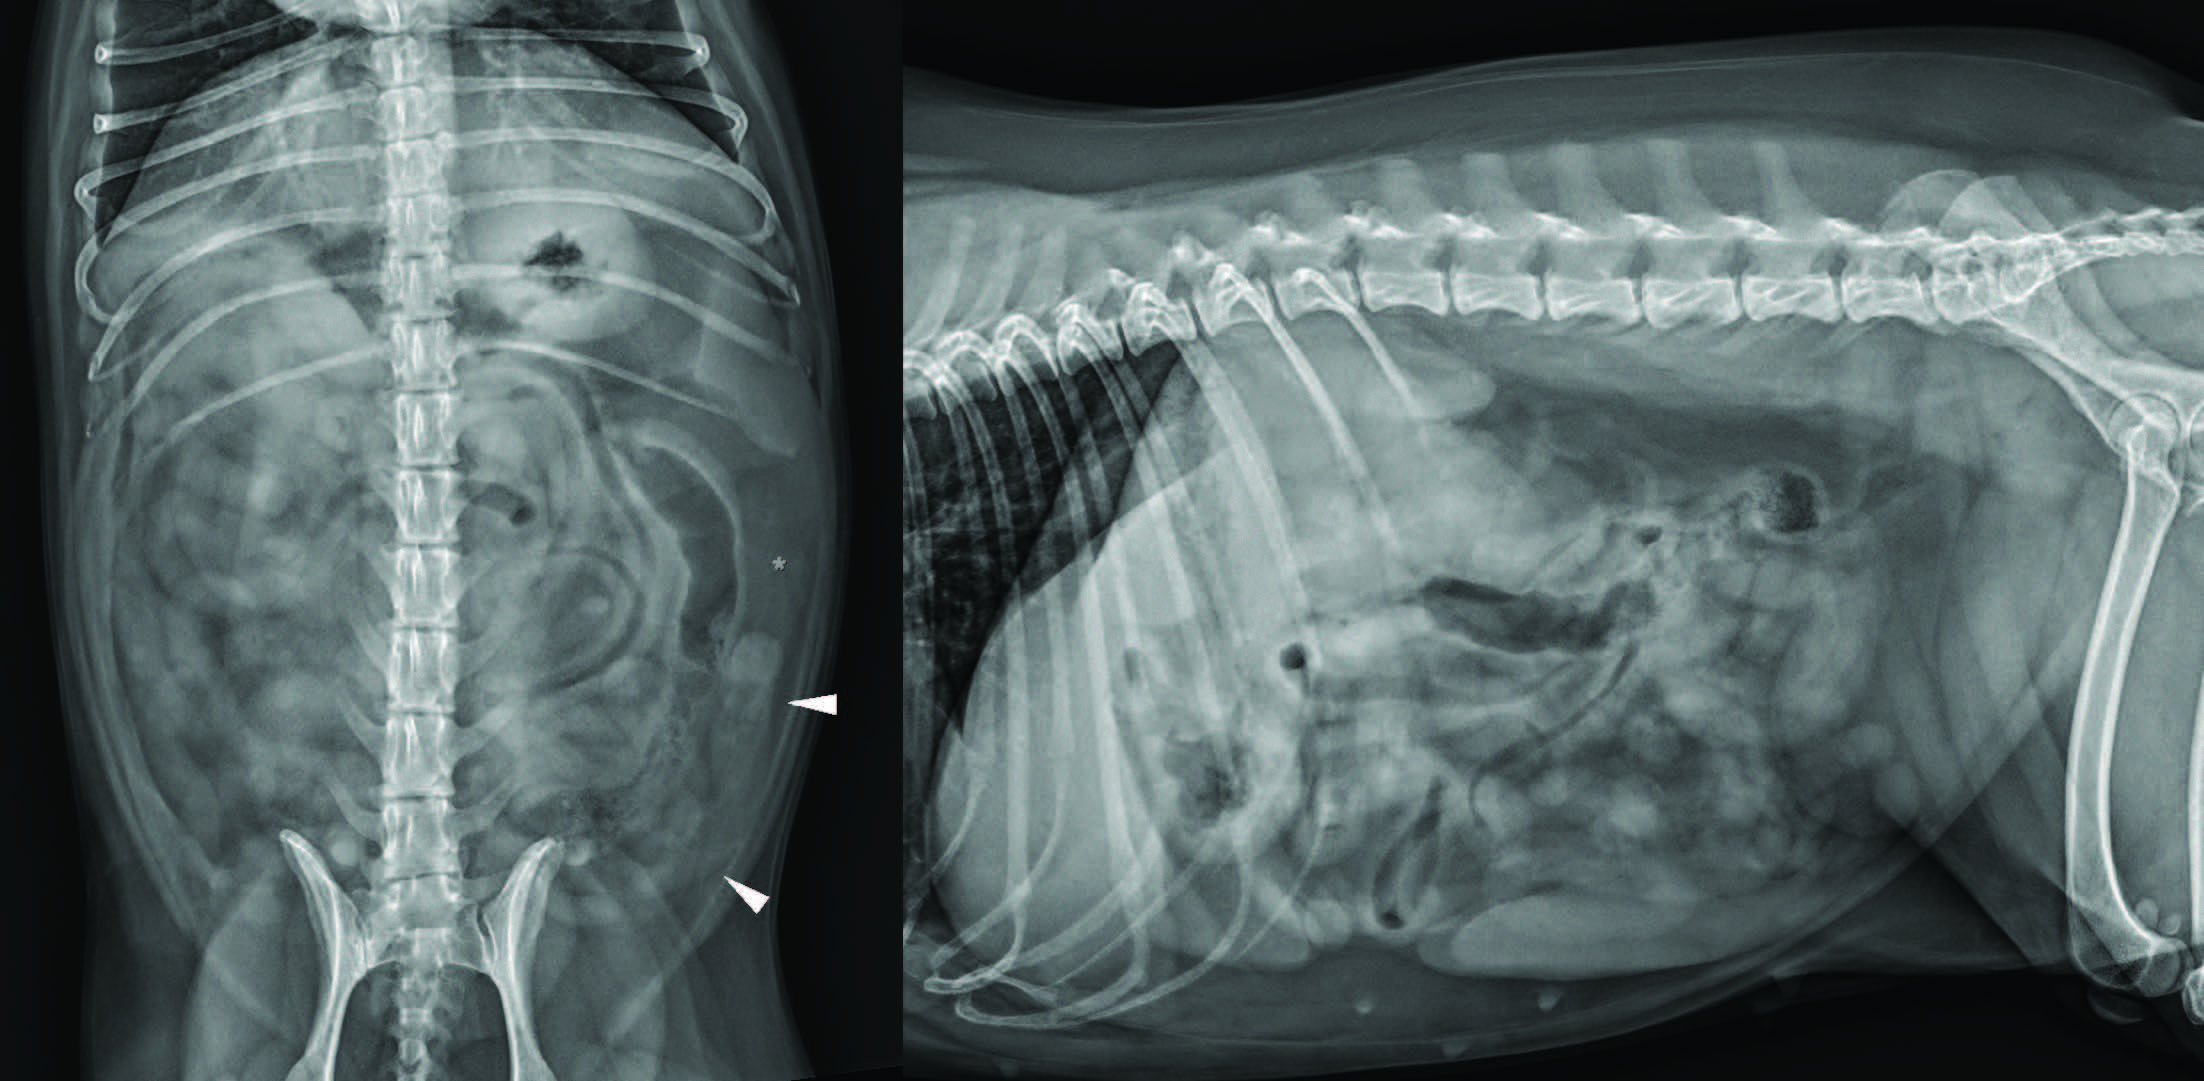

腹部X线片可见腹膜左侧尾外侧纵向结构,符合扩张的左侧子宫角,伴邻近浆膜细节轻度丢失(图1)。右侧前腹部未见病变。

图1. 腹背位(左)及左侧位(右)X线片。可见腹膜左侧尾外侧纵向结构,符合扩张的左侧子宫角(箭头),伴邻近浆膜细节轻度丢失(星号)。右侧卵巢区域未见明显病变。